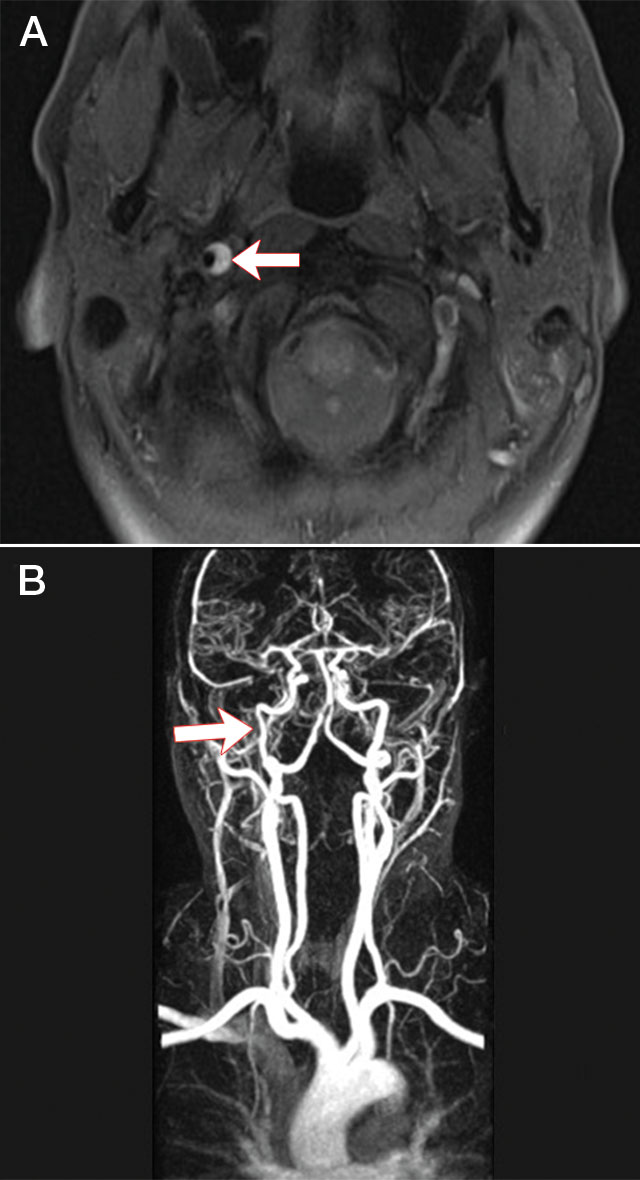

A 42-year-old woman with no vascular risk factors was admitted with neck pain and right Horner syndrome after riding a roller coaster. Magnetic resonance imaging (MRI) of her neck showed a characteristic crescent-shaped intramural haematoma in the right internal carotid artery1 (Figure, A), confirmed by magnetic resonance angiogram (MRA) (Figure, B). T1-fat-suppressed MRI and arterial wall imaging are currently the most sensitive techniques for diagnosis of dissection. Riding roller coasters has been associated with shearing neck injury leading to cervical artery dissection.2 Our patient was treated with warfarin for 6 months, leading to the intramural haematoma resolving and the Horner syndrome greatly improving.